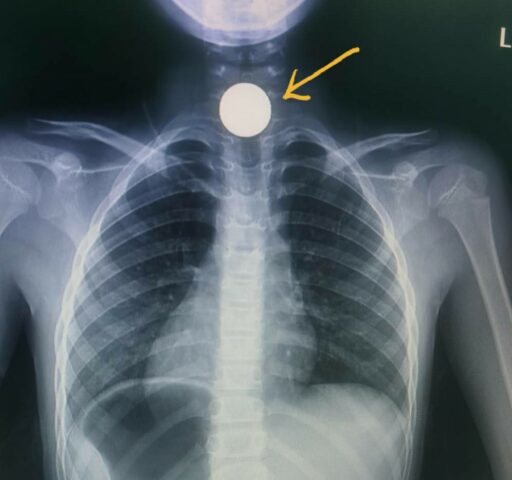

เมื่อ 4 พ.ย.2563 นพ.อารักษ์ วงศ์วรชาติ ผอ.รพ.สิชล จ.นครศรีธรรมราช ได้โพสต์ข้อความพร้อมภาพลงเฟสบุ๊คส่วนตัวชื่อ “Arak Wongwarachat” ข้อความว่า…#กลืนเหรียญ5บาทติดค้างในคออีกแล้ว เคสกรณีตัวอย่างเตือนผู้ปกครองที่ดูแลเด็ก เด็กผู้ชายอายุ 6 ปีเศษ ขณะเล่นกับเพื่อน มีเหรียญ 5 บาทติดกระเป๋า จึงเอามาเข้าปากอมไว้เล่น ๆ ช่วงที่เล่นเพลิน ๆ เผลอกลืนลงไป จนติดคอ ยิ่งพยายามกลืนยิ่งเจ็บ จนต้องทรุดตัวลงนั่งอาเจียน น้ำลายไหลฟูมปาก อึดอัดในคอมาก พูดไม่ค่อยออก กระทั่งผู้ปกครองมาพบจึงรีบพาส่งโรงพยาบาลใกล้บ้าน แพทย์ห้องฉุกเฉินเอกซเรย์ทรวงอก เห็นเหรียญติดอยู่ที่คอส่วนบน แต่อ้าปากใช้ไฟฉายส่องจะมองไม่เห็น เนื่องจากอยู่ลึกลงไปไม่สามารถเห็นได้ด้วยตาเปล่า

แพทย์จึงส่งต่อไปที่โรงพยาบาลสิชล แพทย์เวรส่งปรึกษาแพทย์ผู้เชี่ยวชาญด้าน หู คอ จมูก ให้เตรียมเข้าห้องผ่าตัดทันที งดน้ำ อาหาร ให้สารน้ำทางเส้นเลือดดำ เข้าห้องผ่าตัดต้องใส่ท่อในทางเดินหายใจเพื่อดมยาสลบ และป้องกันการสำลักเศษอาหาร น้ำ สิ่งแปลกปลอม เข้าหลอดลม จะยิ่งอันตราย และแพทย์ใช้เครื่องมือส่องกล้องชนิดพิเศษในหลอดอาหาร เตรียมไว้หลายขนาดให้พอดีกับเด็ก เห็นเหรียญติดค้างในแนวขวาง กดทับหลอดอาหารจนเป็นแผลลึกแต่ยังไม่ทะลุ ใช้เครื่องมือคีบดึงออกมาได้อย่างปลอดภัย หลังออกจากห้องผ่าตัดให้น้ำเกลือต่ออีก 1 วัน ให้ยาระงับปวด ยาปฏิชีวนะ เมื่อเห็นว่าไม่มีภาวะแทรกซ้อน เริ่มให้จิบน้ำ กินอาหารเหลว อาหารอ่อนได้ ที่อันตรายคือ อุดหลอดลมจนหายใจไม่ออกเสียชีวิตได้ง่าย ๆ หรือทิ้งไว้นานจนกดทับหลอดอาหารเป็นแผลทะลุ หรือบางรายผ่านหลอดอาหารไปได้แต่ไปติดค้างในลำไส้เล็กทำให้ลำไส้อุดตันจนต้องผ่าตัดใหญ่ในที่สุดก็มี